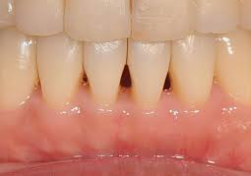

찬물을 마시거나 양치질을 할때 갑자기 이가 시린 증상이 있습니다. 이럴때 시린 부위의 잇몸이 내려앉아 있는 현상을 볼 수 있습니다. 나이가 들어갈수록 잇몸이 내려가게 되고 점차 치아의 뿌리까지 보여질 수 있다고 합니다. 잇몸이 있어야 치아도 버틸수 있습니다. 잇몸 내려앉음 증상의 원인과 치료방법, 예방법에 대해서 알아보도록 하겠습니다.

치과의사 선생님의 이야기를 들어본 결과 내려앉은 잇몸은 다시 올리는건 어려우며 현재를 유지하는 방법이 최선이라고 합니다. 잇몸 내려앉음 치료방법에는 앞서 소개된 원인 중 하나인 치석을 제거하는 방법입니다. 위에 오른쪽 사진을 보시면 스케일링 전/후 인데요. 오른쪽 스케일링 후 사진을 보면 치석을 제거하니 치아 사이사이 비어있는 모습이 보입니다. 이렇듯 치석이 많이 끼게되면 잇몸이 내려앉기 때문에 치석이 많이 끼이기 전에 스케일링을 받는 것이 좋습니다. 스케일링은 1년마다 1번씩 보험처리가 가능하기 때문에 1년에 1번 스케일링을 꾸준히 받아주시는게 좋습니다.